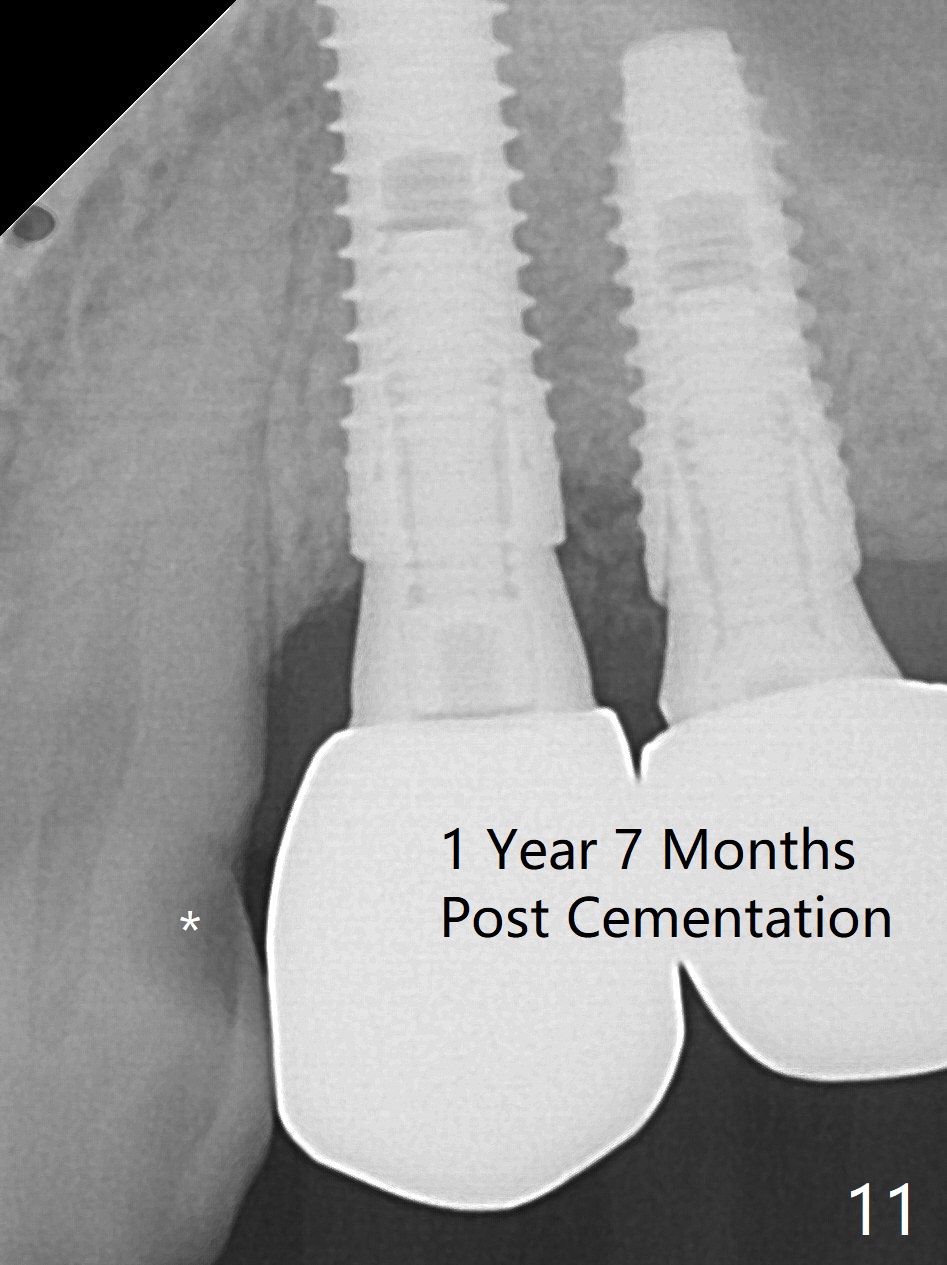

The buccal gingiva at #12 with vertical root fracture looks unhealthy (Fig.1). Osteotomy at #13 is initiated prior to #12 extraction. In fact the osteotomy happens in the extensive defect associated with #12 (Fig.2 red dashed line). To obtain primary stability, the osteotomy at #12 needs to be long, while that at #13 needs two-pointed fixation (Fig.3 *). After adjustment of trajectory at #12 and increase in diameter of the osteotomy at #13 (Fig.4), a 3.8x15 and 3.8x10 mm implants are placed (Fig.5). Following adjustment of implant depth (Fig.6), the implant at #12 becomes loose, while that at #13 tightens. With placement of abutments, an immediate splinted provisional is locked in place to stabilize the loose implant at #12 (Fig.7). The patient complains of cold sensitivity in the upper left quadrant, possibly related to the fact that the implant at #12 is close to the apex of the tooth #11. The position and trajectory of the initial osteotomies should be changed as shown in Fig.8 (white lines, as compared to Fig.2). There is no sensitivity 1 month postop. Impression is taken 4 months postop (Fig.9) after #13 mesiobuccal margin prep. The implants were placed too close to each other. The abutment screw at #13 is retightened 8 months post cementation. There appears no bone loss 9 months post cementation (Fig.10), while the tooth #11 has periapical infection with DL caries 1 year 7 months post cementation (Fig.11).